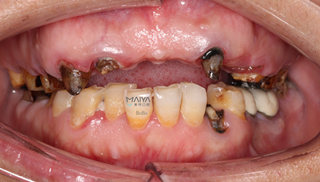

来自香港的郄女士是位时尚的爱美人士,早在10年前就意识到牙齿对人容貌的重要性,一口整齐洁白的牙齿实在令人加分不少,而偏偏自己的牙齿却因发黄、畸形、排列不齐常常令她感到困扰,又因蛀牙饱受折磨,爱美的她干脆心一横,不管好牙、坏牙,把上颌包括门牙在内牙齿全换成烤瓷冠。但由于当时条件的限制,选择材料和技术不过关,做的烤瓷冠密闭性不好,以致牙齿里面的牙根逐渐发炎、腐烂以及松动。

一口糟糕的烂牙,让郄女士痛苦不堪,她说:“现在根本没办法和同事、家人一起吃饭,吃的慢不说,稍硬一点的米饭都能让牙齿自然脱落,别提有多尴尬了,而在日常生活中,除了吃流食外,还不敢张口笑,怕人家一见到我的牙齿就纷纷议论”。

通过科学的德国卡瓦数字化口腔CT三维检测,麦芽口腔种植医师指出,由于长期对口腔疏于护理,郄女士的口内存有大量残根烂冠,咬颌空间不足,种植难度非常大,且上颌骨前突,为进一步达到美学效果,需要进行上颌前牙区牙槽骨修整术,整个治疗方案对医生的技术要求非常高。